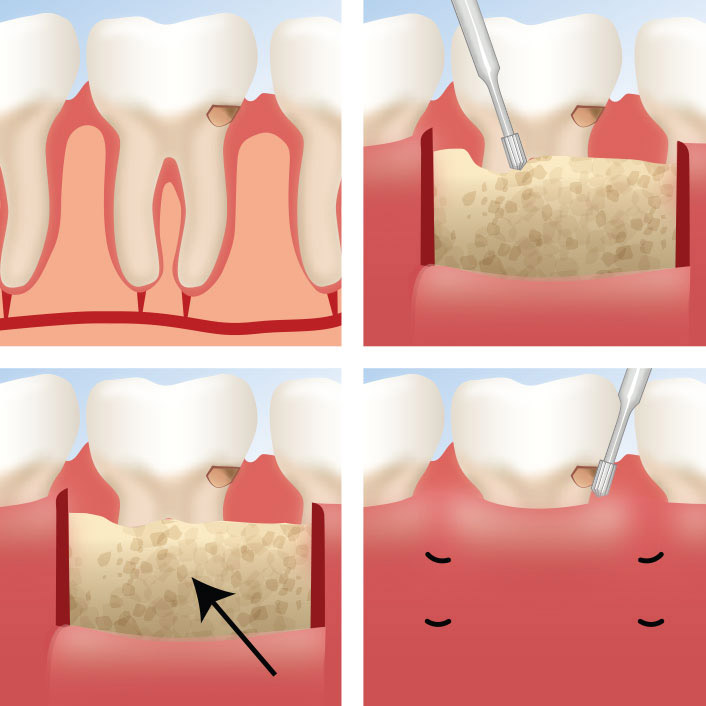

Early-stage gum disease (gingivitis) can often be managed with a professional cleaning and improved home care. More advanced disease may require scaling and root planing, surgical pocket reduction, or regenerative procedures. The sooner you come in, the more options are available — and the more of your natural teeth we can preserve.